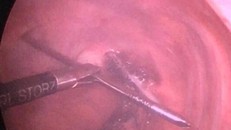

Hình ảnh gỡ chiếc đinh khổng lồ ra khỏi nhu mô phổi - Ảnh: VTC News

Chiếc đinh 12cm xuyên qua phổi, đâm vào tuỷ sống người đàn ông

20/08/2018 09:45

(Ngày Nay) - Chiếc đinh cố định xương đòn bị gãy của người đàn ông đã tự di chuyển qua đỉnh phổi, đâm xuyên qua tủy sống.